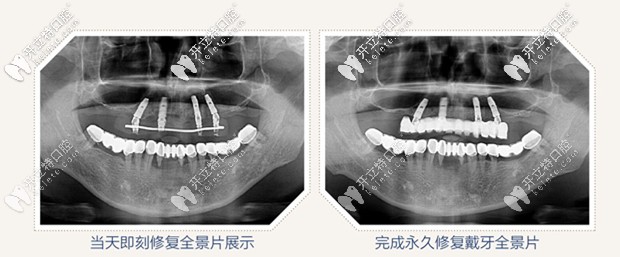

全景片圖示

all on 4即刻種植,只需要植入4顆種植體,就把老爸上半口牙就全給修復(fù)啦,并且是當(dāng)天修復(fù),當(dāng)天戴牙啊,感覺太神奇啦!

All-on-4即刻種植牙效果圖

給老爸做的all on 4半口即刻種植牙花了10萬左右, 價(jià)格還是可以接受的,畢竟這做完種植牙的效果擺在這呢,上下半口牙齒恢復(fù)了咀嚼功能,近距離交談也看不出來做了種植牙,還有感覺老爸瞬間年輕了許多。